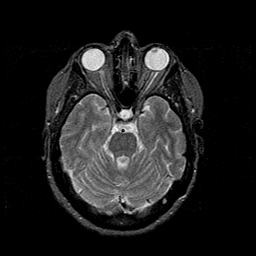

MR Study #1 -- Slice #19

[Home][Help][Clinical][Tour 1][Tour 2][Tour 3] Slice 19